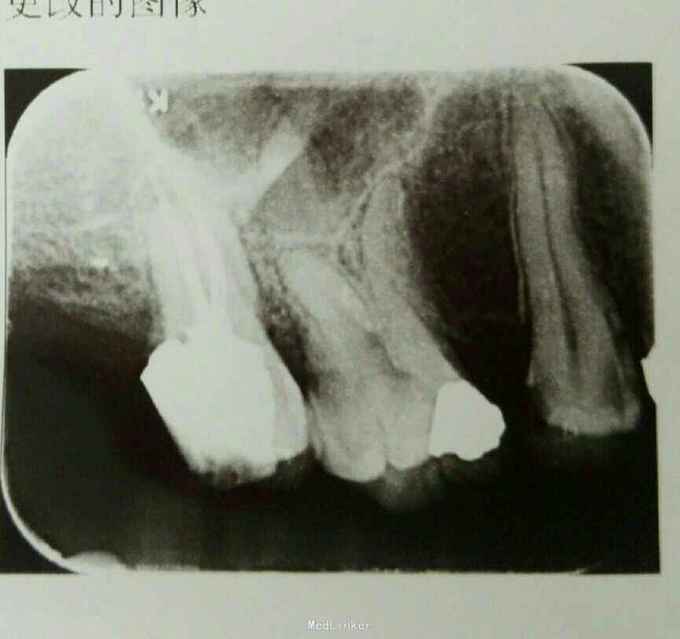

诊断:17牙髓坏死 治疗计划:17根管治疗 处置:17开髓,去腐,揭顶,大量交替冲洗,探及颊腭侧两个根管口,沿牙冠中央颊舌向对称分布,未见第三个根管口,置CP棉球,氧化锌暂封 一周后复诊:17去除暂封,测根长,B=18mm,P=19mm,K锉加EDTA扩大根管,发现B根管口远中间隔1mm处有一个疑似根管口,C锉探入,测得根长17.5mm,扩大MB,DB至30#,P扩大至40#,冲洗,置CP棉球,氧化锌暂封 一周后复诊:试主尖,冷侧压充填,氧化锌暂封,观察一周后建议全冠修复

讨论:此例患者诊断明确,诊治过程属于常规过程,上颌7根管解剖形态常规来说有3个根管,但是根管口形态变异较大,在这个病例中,颊侧近远中根管口仅间隔0.5mm,容易遗漏,因此行仔细探查根管口,防止遗漏,导致治疗失败